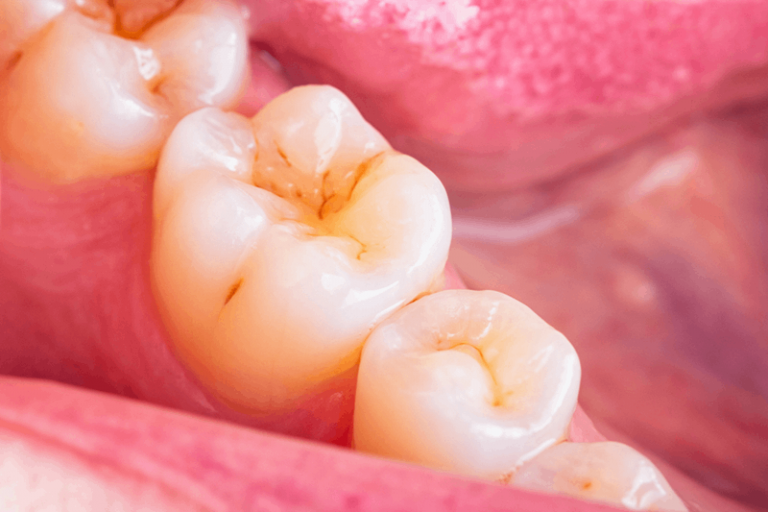

病患初期僅侵蝕琺瑯質時,可以沒有明顯的症狀,只有如牙齒帶黃色、牙齒表層有磨損現象、牙齒邊有破裂、牙齒看來「薄」了等。但當侵蝕到象牙質時,患者會感到牙齒酸軟。此外,在進食冷、熱甜點或酸性食物及飲品;刷牙或使用牙線時會感到刺痛。由於牙齒酸蝕症是慢性的,直到出現遇冷、熱、酸、甜,牙齒敏感症狀出現才會引起注意,而出現這種情況時,可能已經影響到牙齒的咀嚼功能。而且牙齒酸蝕造成的破壞是無法逆轉的,琺瑯質一旦流失就無法復原或再生。